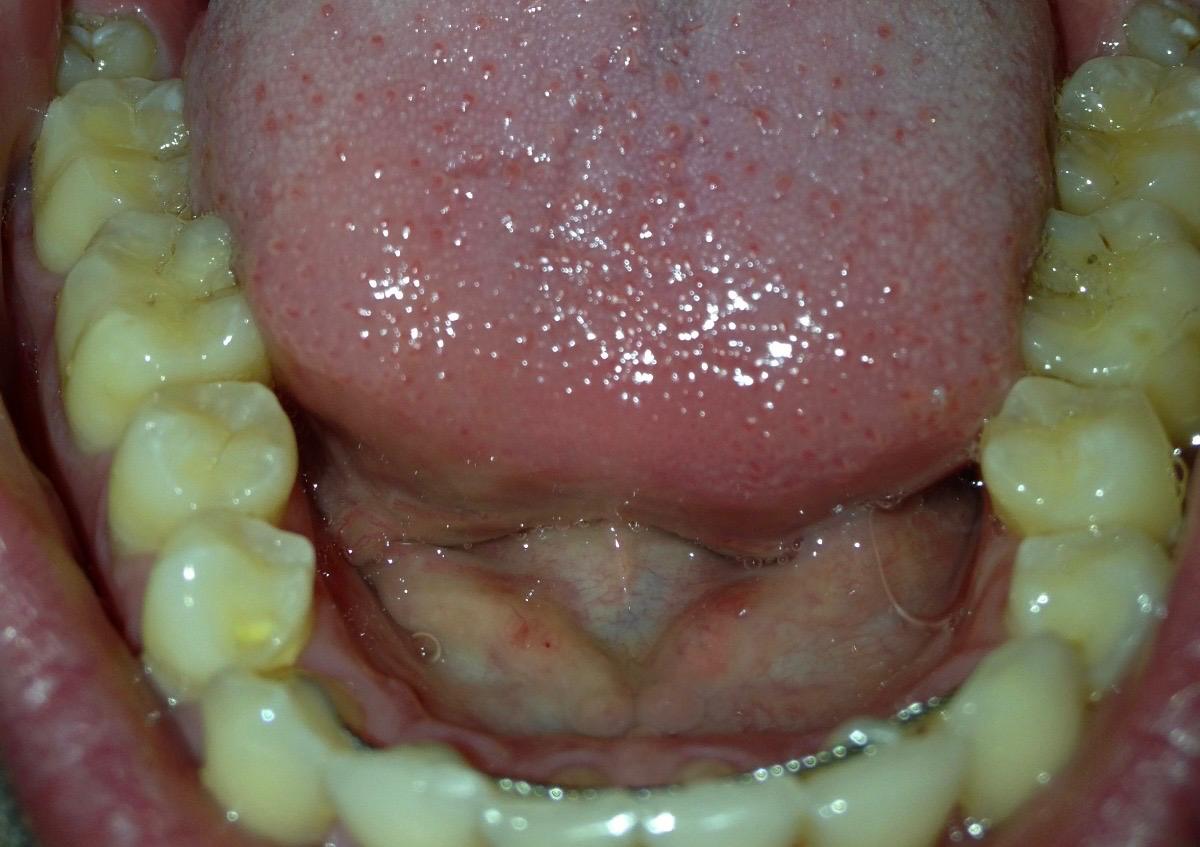

Ik had in april dit jaar al een vraag gesteld in dit forum over mijn mogelijke erosie, u gaf toen aan dat er enige slijtage was. Ik heb totaal geen idee hoe het kan zijn ontstaan, omdat ik mijn hele leven al zowat geen suikers of prik of zure dranken nuttig. Mijn tandartsen en mondhygienisten hebben er ook NOOIT wat over gezegd. Hierbij een foto van 2015 en 2025 onderkaak tanden. Ik zie in die 10 jaar geen verschil. Is het echt flinke slijtage of valt het mee? Wat betreft mijn botniveau, heb ik inderdaad te horen gekregen dat er sprake is van lichte botafbraak, ik gebruik nu elke dag ragers. Heb in het verleden ook een beugel gehad, zou dat ook voor veranderingen in het bot kunnen zorgen? x-fotos van mijn rechter kaak uit 2010 en eind 2024.

Op grond v deze foto's moeilijk te zeggen maar lijkt meer.

Lijkt de erosie meer te zijn bedoel je? de tweede foto is iets warmer dan de eerste omdat het twee verschillende camera's zijn, maar ik zie persoonlijk geen verschil, hoop dat het in ieder geval gestopt is. En wat betreft de x-foto's, de tweede is recent en de eerste is van 14 jaar geleden. En wat betreft mijn pericoronitis, pijn is volledig weg, maar het tandvlees daar is nog zacht en niet strak tegen de verstandskies aan. Is dit een probleem en gaat dit nog over? Ga mijn verstandskiezen in 2026 wel verwijderen, maar wil wel weten of het een probleem is dat het tandvlees daar zacht is.

oke, maar toen (in april) gaf u aan dat u dat u vond dat ze gelijk zijn gebleven. (het ging om dezelfde foto's). Daarnaast gaf u aan dat het wel mee viel. Maar goed, hoop dat het daadwerkelijk meevalt en gelijk is gebleven, want mijn eetgewoontes zijn buitengewoon goed. Fijne feestdagen toegewenst.